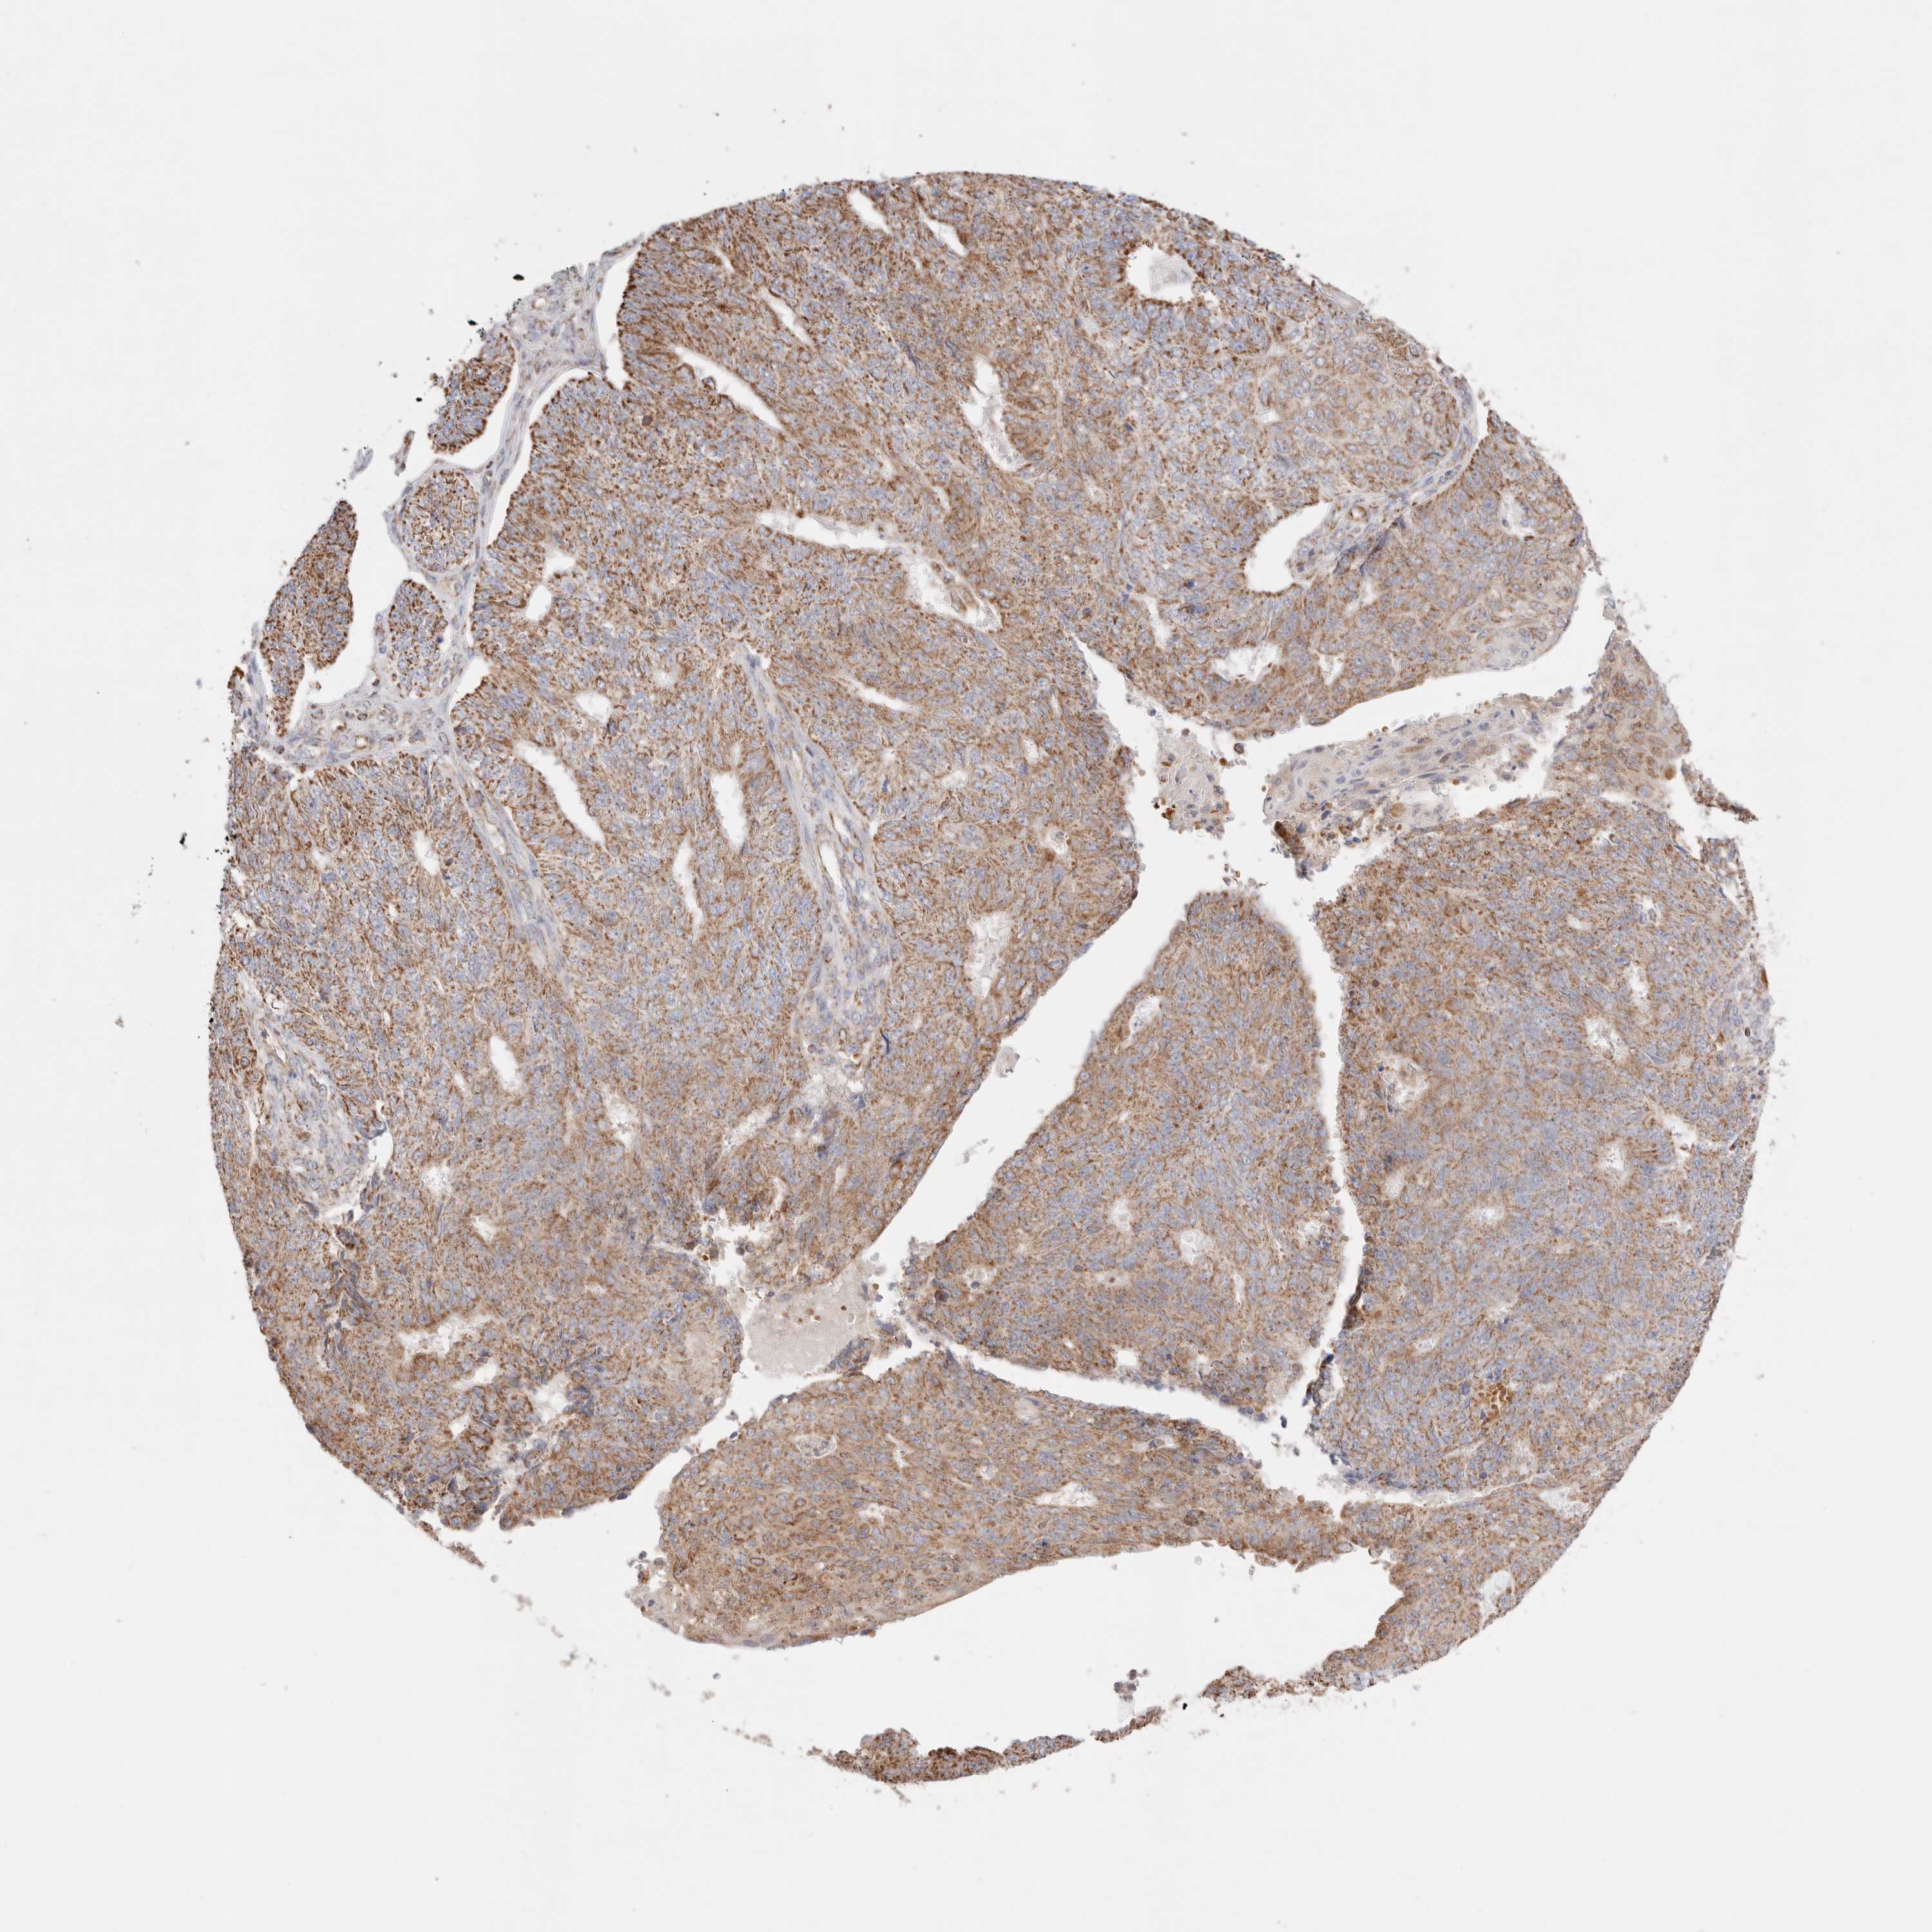

ENDOMETRIAL CANCER - Protein expressioni

A mouse-over function shows sample information and annotation data. Click on an image to view it in a full screen mode. Samples can be filtered based on level of antibody staining by selecting one or several of the following categories: high, medium, low and not detected. The assay and annotation is described here.

Note that samples used for immunohistochemistry by the Human Protein Atlas do not correspond to samples in the TCGA dataset.

Antibody stainingi

Antibody staining in the annotated cell types in the current human tissue is reported as not detected, low, medium, or high, based on conventional immunohistochemistry profiling in selected tissues. This score is based on the combination of the staining intensity and fraction of stained cells.

Each image is clickable and will lead to virtual microscopy that enables deeper exploration of all samples and also displays staining intensity scores, fraction scores and subcellular localization as well as patient and tissue information for each sample.

Antibody HPA027019

Staining

High

Medium

Low

Not detected

Intensity

Strong

Moderate

Weak

Negative

Quantity

>75%

75%-25%

<25%

None

Location

Nuclear

Cytoplasmic/membranous

Cytoplasmic/membranous,nuclear

Adenocarcinoma, NOS

Adenocarcinoma, metastatic, NOS